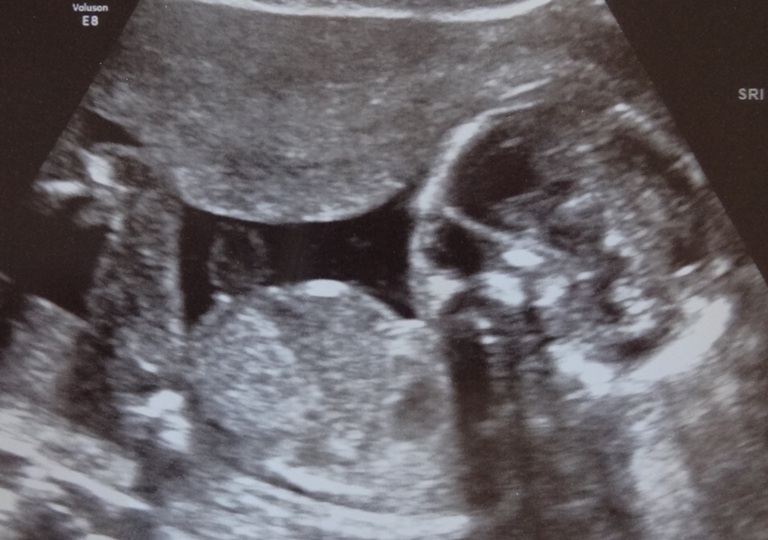

Today we had our ultrasound, I'm at 17 weeks but the measurements said 18 weeks. I tried to look for three lines or a little penis on the potty shot, but could only see two lines? Anyway, we did not get any potty shots printed, so will upload a few profile shots instead. Please tell me what you think, and what you're basing it on (any method/theory is welcome).

Best skull picture;